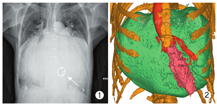

患者女,68岁。胸闷,气喘7年,加重3个月余就诊。体检:颈静脉充盈,双肺少量湿啰音,肝脏肿大肋下3 cm、剑突下4 cm。既往史:2007年行二尖瓣机械瓣置换术,接受规范抗心力衰竭药物治疗4年。心电图:心房颤动,Ⅲ度房室传导阻滞。胸部X线及CT:心脏明显增大(图1,图2)。经胸超声心动图:①二尖瓣位人工机械瓣功能良好;②左房显著增大(前后径11.9 cm,左右径16.6 cm,上下径15.4 cm);③三尖瓣中度关闭不全;④左室收缩功能测值正常(射血分数62%),舒张功能减低(Ⅲ级,限制性充盈障碍),右室收缩功能正常范围(右室面积变化率39%,三尖瓣环收缩期位移20 mm,三尖瓣环收缩期运动速率18 cm/s)。门诊以"二尖瓣置换术后巨大左房,肺动脉高压,心功能Ⅲ级"收入院。入院后实验室检查B型脑尿钠肽238.4 ng/L,6 min步行距离325 m。患者因严重舒张功能障碍致心力衰竭表现,且合并恶病质、白细胞低及凝血功能紊乱,接受常规体外循环外科手术治疗风险极高。经多学科团队讨论后,拟行心房分流器置入降低左房压力,以改善患者症状。

心房分流器置入过程的超声引导与监测:手术开始前,经食管超声多切面观察,排除心腔内血栓、房间隔缺损及房间隔膨胀瘤,同时再次确定适应证。术中经食管超声引导下,房间隔穿刺鞘沿导丝进入右房(图3A),穿刺鞘尖端于卵圆窝后下部进行穿刺(图3B)。穿刺后,预先塑形的加硬钢丝经房间隔穿剌部位至左心房内,其后递送10 mm外周动脉球囊至房间隔处,以8个标准大气压行反复球囊扩张。超声实时监测扩张部位、过程、大小。退出球囊后送入输送系统,选择20-6 mm的D-shant心房分流器,在经食管超声监测下,将其释放于房间隔两侧(图4A,B),经食管超声显示分流器形态、位置正常,分流孔径约6 mm,并清晰显示左向右分流信号(图5),三维超声观察分流器形态及其与周围组织毗邻关系;即刻右心导管测压,左房压由分流器置入前15 mmHg降至置入后8 mmHg(1 mmHg=0.133 kPa),释放分流器。术后送监护病房观察。患者自诉症状明显改善,1 d后从监护室转回普通病房,3 d后出院。3个月后复查心脏超声,分流器形态位置正常,患者自觉生活质量提高。